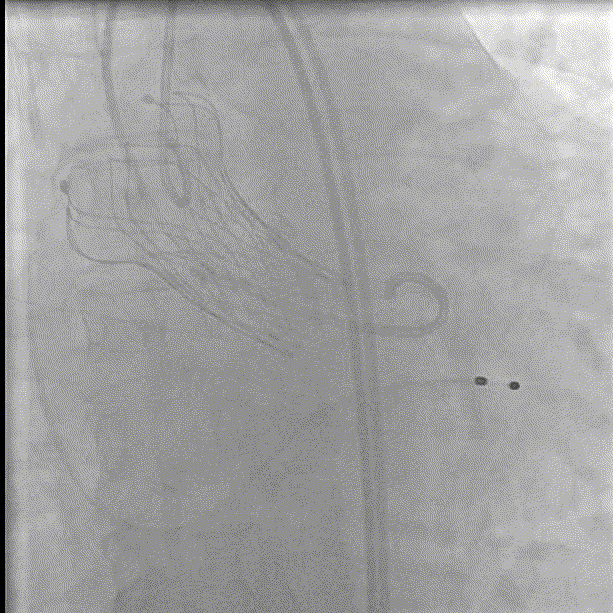

支架预埋

瓣膜首次定位释放

瓣膜释放至2/3

回收瓣膜再释放

多体位下观察植入深度

释放完成